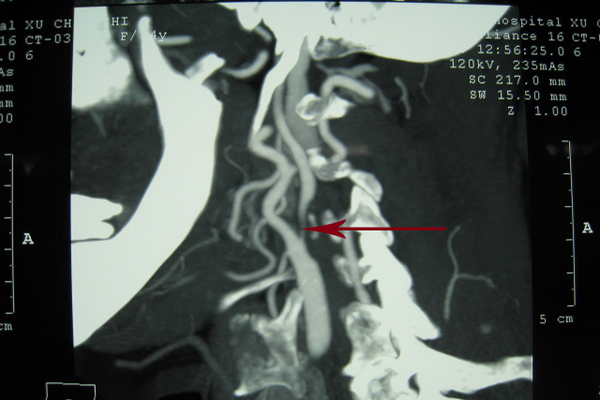

CT——颈总动脉末端及颈内、颈外动脉起始段重度狭窄

超声——颈动脉分叉处重度狭窄